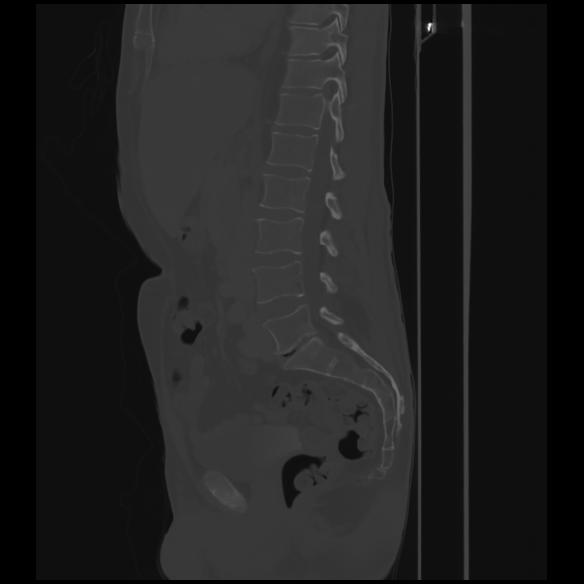

7 CUERPO,CE,Sagittal,3.000,CUERPO,Sagittal,